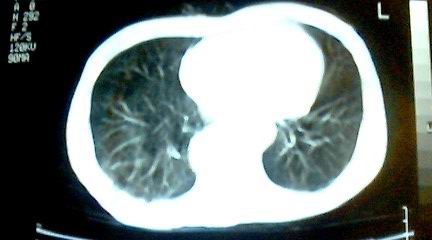

标题: CT25218:请教!胸部CT,胸8椎体骨质破坏,伴周围软组织肿。 [打印本页]

标题: CT25218:请教!胸部CT,胸8椎体骨质破坏,伴周围软组织肿。

患者,女41岁,肢体乏力。

双肺及胸椎结核。

双肺及胸椎结核。支持!

两肺上叶继发性肺结核;胸椎结核并椎旁寒性脓肿形成。

支持,不过本人还要说有的占位和其它炎症也这样,你要是看到1000个这样的都报结核了,我保你其中必有错的